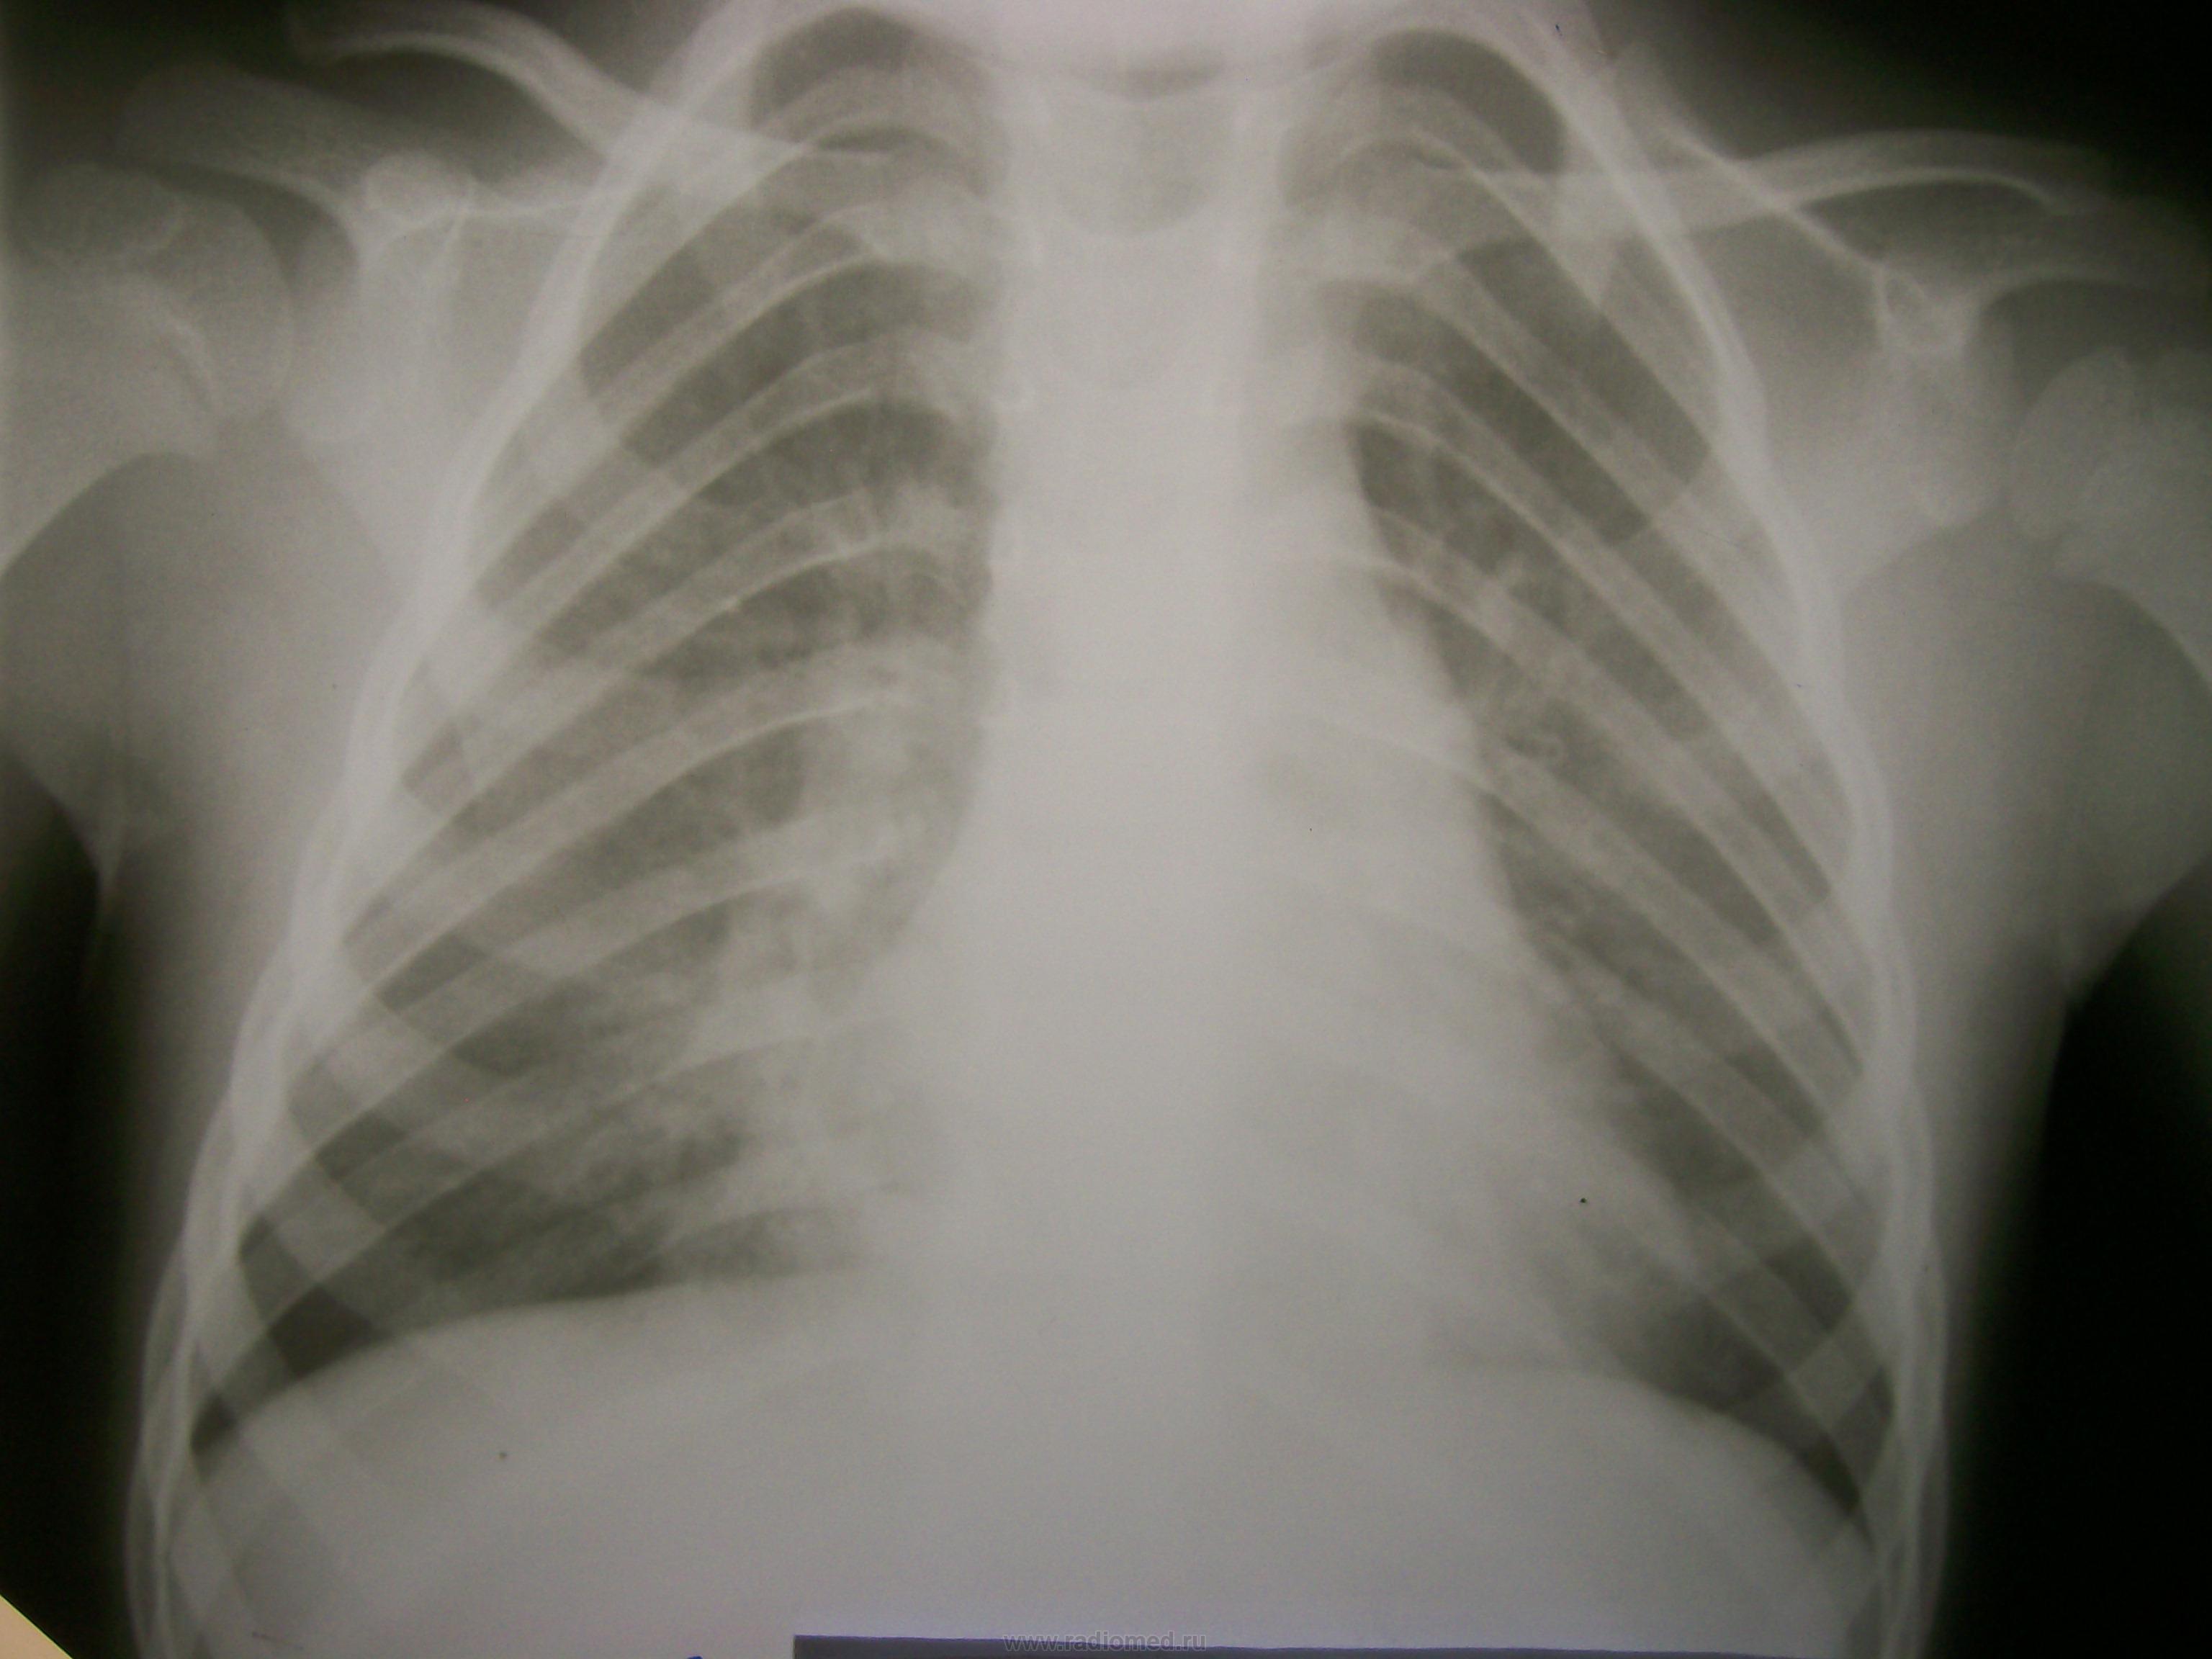

До этого с 21.05 по 28.05 лежал в детском отделении и по снимкам я ставила нижнедолевую пневмонию справа.

Самостоятельно родители свозили реьенка в область. Рентгенолог областной детской больницы описала, что инфильтрации нет, а есть сгущение легочного рисунка в нижней доле справа. И в заключении выставила " признаки обструктивного синдрома".

Как трактовать изменения на сегодняшних снимках и майских?

Первые 2 снимка сегодня, вторые 2 майские.

Написал бы р-признаки ателектаза средней доли правого легкого. Если есть возможность, сделал бы снимки по Флейшнеру.